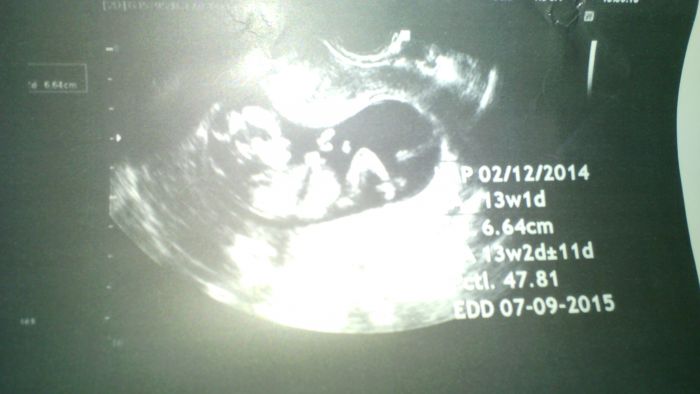

Lucii: tady je náš prďola,přitom nepřijde,že by tam bylo hodně místa a plodovky